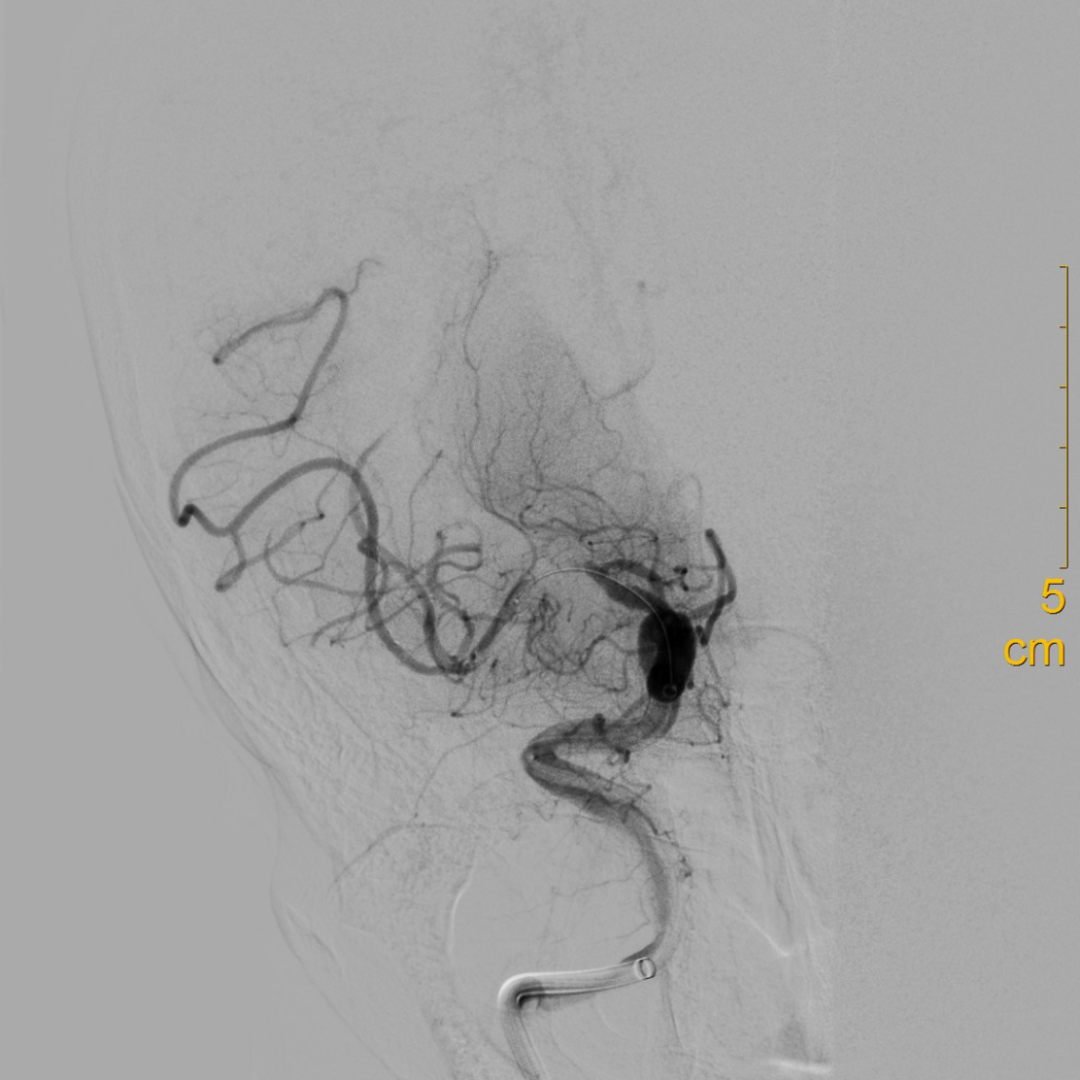

扩张后造影见血流改善,支架内未见明显血栓影。

什么叫桡鞘【例久弥新】寻道于桡——瑞康通5.5F IntroSky X导管鞘经桡动脉行右侧大脑中动脉取栓一例_https://www.jmylbn.com_新闻资讯_第22张

观察10分钟回收支架后,继续观察15分钟提示血流良好。